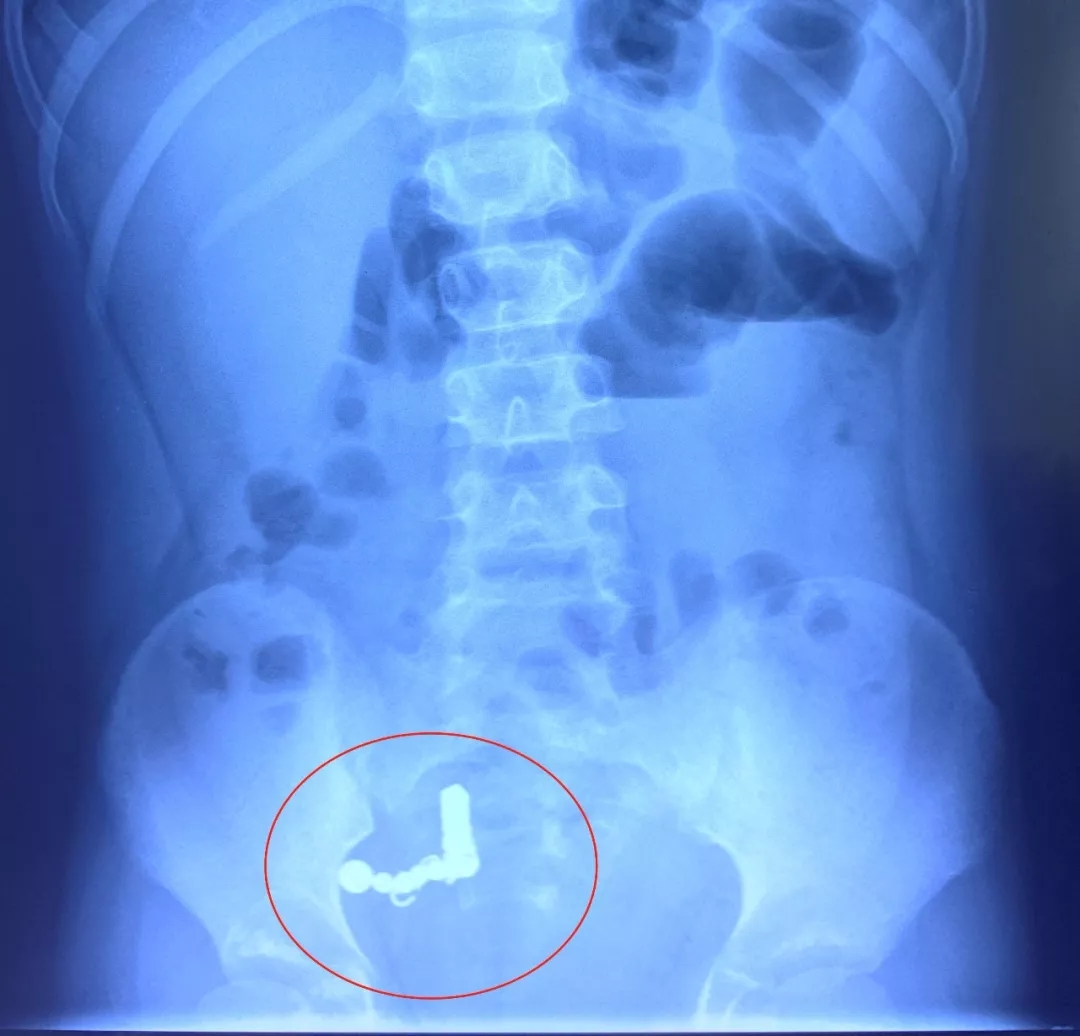

肠道8处穿孔 内藏18枚异物

经过一系列检查

医生发现小博的肠道内有十多枚异物

7月16日凌晨1点50分

孩子被推入手术室

医生为孩子实施消化道异物急诊手术

手术中

医生竟然在小博体内发现磁性方块4块、

磁性圆珠7枚、铁丝圈7个,

肠管穿孔达8处之多!